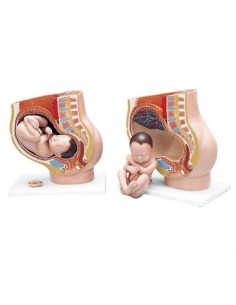

Dal cranio in 22 parti con incastri magnetici ai modelli di colonna vertebrale, da quelli di articolazioni a quelli di cuore, ogni pezzo della nostra collezione è progettato per un’immersione totale nello studio dell’anatomia umana. I nostri modelli, realizzati tramite scansioni di ossa vere, garantiscono un’esperienza tattile autentica e una fedeltà di peso quasi identica agli originali.

Essenziali per studenti e professionisti, i nostri modelli anatomici sono strumenti didattici che permettono di osservare le strutture anatomiche con precisione, eliminando la necessità di dissezioni o studi invasivi. Sono inoltre utili per spiegare ai pazienti le patologie, rendendo la comunicazione più efficace e risparmiando tempo prezioso.